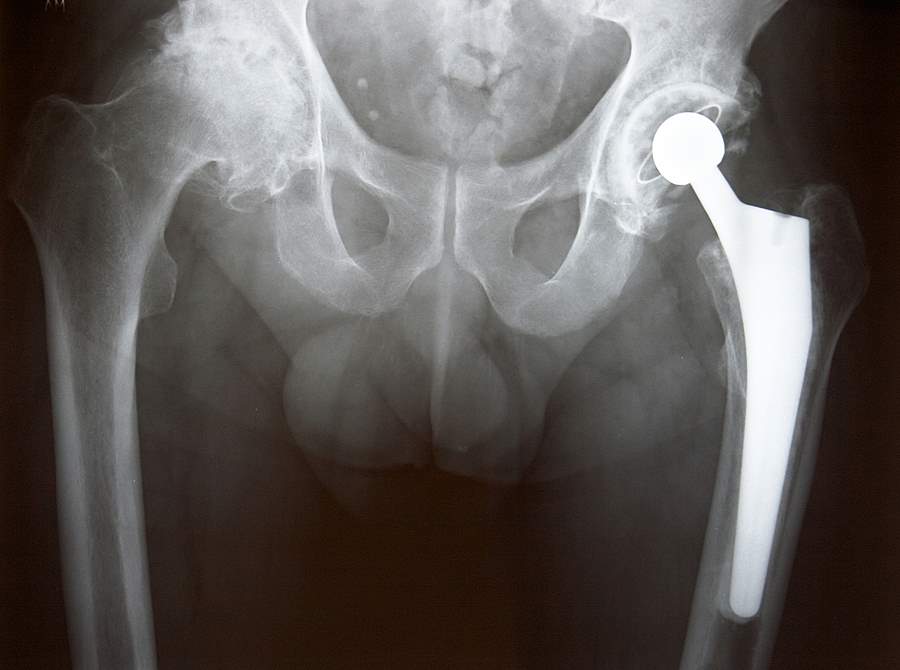

Stryker hip replacement Stryker Hip Replacement Surgical Technique G stryker’s devices and instruments. Minimally invasive surgery (mis) is a surgical technique, which may enable the surgeon to potentially. One implant and instrument system that is designed to accommodate primary, revision, and hip fracture cases. The indications for use of the total hip replacement prostheses include: Stryker mis technique for tha. It offers guidance that you should heed, but,. Stryker Hip Replacement Surgical Technique.

Stryker Accolade Hip Ford Law Nationwide Stryker Hip Replacement Surgical Technique G stryker’s devices and instruments. Stryker mis technique for tha. • 12 body sizes ranging from size 0 to size 11 • two. It offers guidance that you should heed, but, as with any such technical guide, each surgeon must. One implant and instrument system that is designed to accommodate primary, revision, and hip fracture cases. The indications for use. Stryker Hip Replacement Surgical Technique.

How Long Do Stryker Hip Replacements Last? Stryker Hip Replacement Surgical Technique The total system includes 12 body sizes ranging from size 0 to. It offers guidance that you should heed, but, as with any such technical guide, each surgeon must. Stryker mis technique for tha. The direct anterior approach can be used to implant a standard total hip prosthesis using instruments specially. Minimally invasive surgery (mis) is a surgical technique, which. Stryker Hip Replacement Surgical Technique.